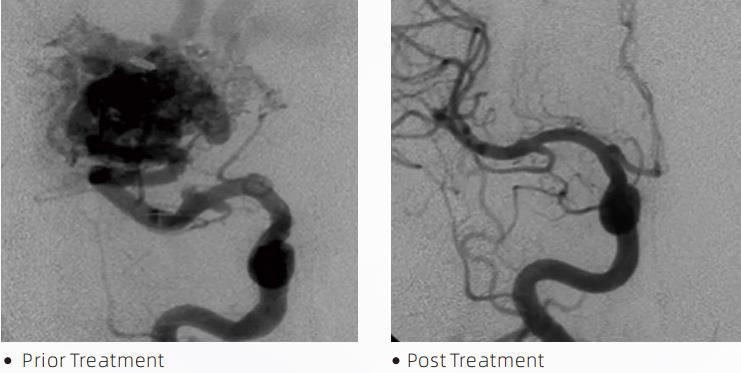

ЛаваТМLiquid Embolic System — це інтервенційна ендоваскулярна терапія для лікування цереброваскулярних вад розвитку. Цереброваскулярна мальформація відноситься до групи доброякісних або злоякісних нервово-судинних аномалій, які можуть призвести до внутрішньочерепного крововиливу, церебрального інфаркту, церебральної ішемії та інших захворювань. Система рідинної емболізації – це медичний пристрій, який вводять шляхом простого внутрішньосудинного введення, який емболізує аномальні церебральні кровоносні судини шляхом введення спеціальної рідини. Рідкий матеріал утворює контрольовану тканинну емболію всередині кровоносних судин, що може зменшити вплив цереброваскулярних вад розвитку на пацієнтів. Для доступу до місця емболізації використовується мікрокатетер для доставки, сумісний з ДМСО, показаний для використання в кровоносній системі. Рідкий емболічний агент Lava — це неадгезивна система рідкого емболічного агента, що складається з сополімеру EVOH (етиленвінілового спирту), розчиненого в ДМСО (диметилсульфоксиду), і суспендованого мікронізованого порошку танталу для забезпечення контрасту для візуалізації під час рентгеноскопії. ЛаваТМдоступний у трьох формах: LAVA-12, LAVA-18 та LAVA-34. LAVA-12: Рекомендується під час живлення дистальних мікросудин і через невеликі годівниці. LAVA-18: Рекомендовано, коли ін’єкції живлення в ніжку будуть проводитися поблизу вогнища; LAVA-34: Рекомендується для емболізації більшого потоку та більших свищевих компонентів.